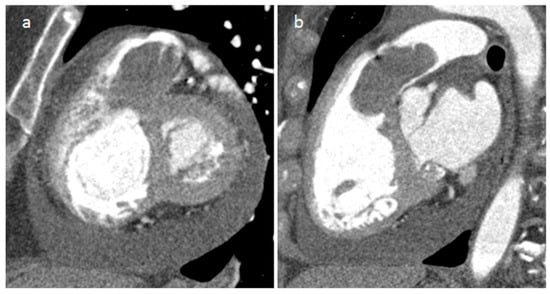

3.1. Thrombus

| Thrombus | Adulthood | LA, LAA (AF) LV (MI) | Asymptomatic, embolic events | Non-enhancing Intracardiac lesion | Acute: Low echodensity, rounded with smooth contours Chronic: High echodensity, linear or crescentic lesions along the endocardial surface | Low attenuation, no contrast enhancement, chronic thrombus may be calcified Usefulness of delayed CT imaging, as in the LAA stasis of blood can simulate a thrombus on early arterial images | Acute: hyper T1w and T2w Subacute: hyper T1w and hypo T2w Chronic: low T1w and T2w No enhancement. |